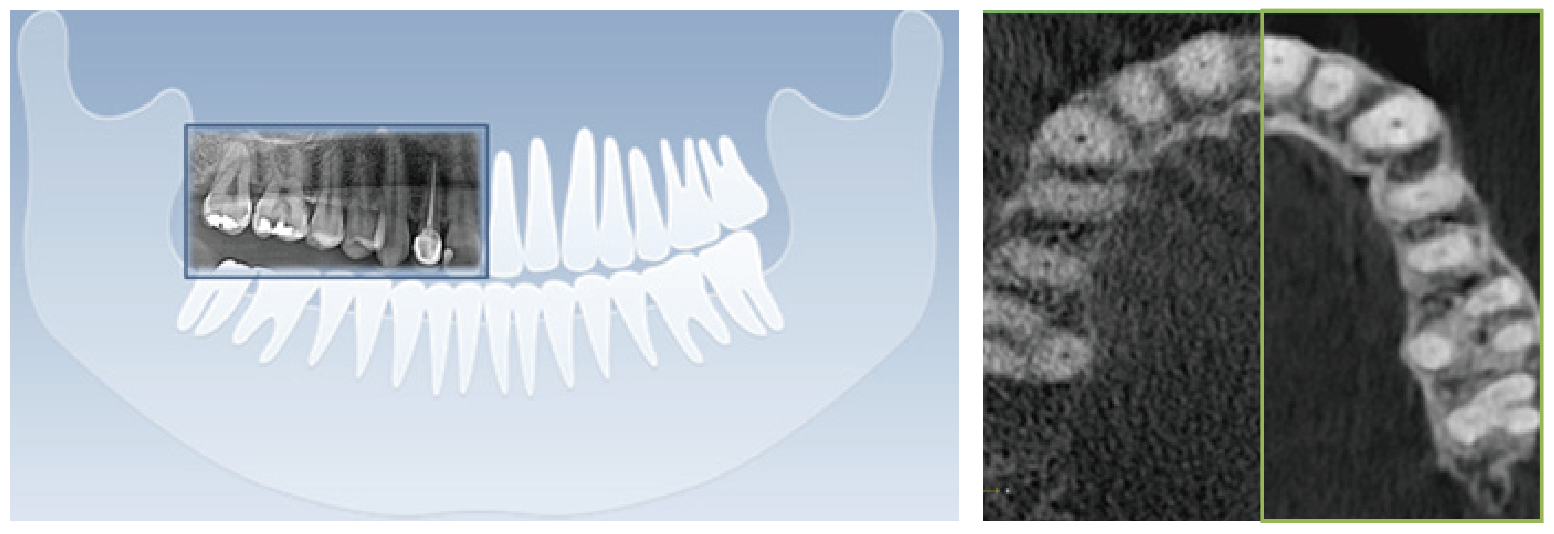

清晰的全景影像

通過多層技術(shù),可以拍攝多張圖像,每張圖像被進(jìn)一步分割。系統(tǒng)會(huì)自動(dòng)選擇最佳焦點(diǎn)將其整合成一個(gè)優(yōu)化的全景圖像。

前牙部畸變縮小,即使不單獨(dú)拍攝小牙片,也能準(zhǔn)確診斷。清晰度可準(zhǔn)確識(shí)別種植體螺紋和內(nèi)部,確保連接程度和斷裂程度。